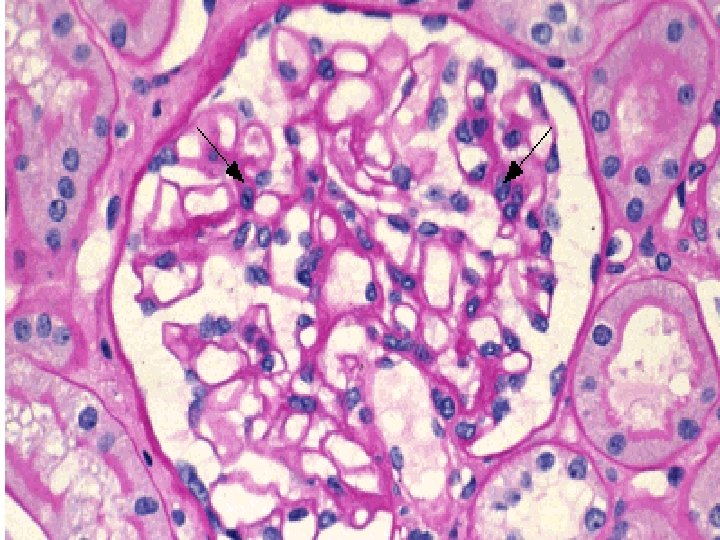

Postinfectious GN